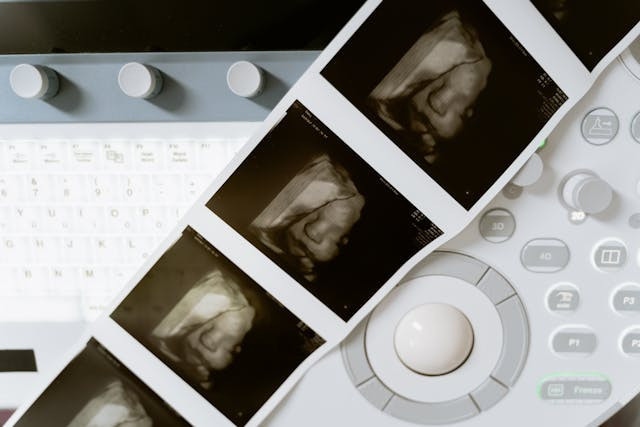

Kondisi gizi ibu hamil berperan besar dalam mendukung pertumbuhan janin, termasuk dalam menentukan berat badan bayi saat lahir. Berat lahir yang optimal sering dikaitkan dengan peluang tumbuh kembang yang lebih baik di masa kanak-kanak hingga dewasa.

Vitamin B kompleks terdiri dari beberapa jenis vitamin yang bekerja sama untuk mendukung fungsi tubuh. Pada masa kehamilan, vitamin ini berperan dalam pembentukan sel darah, metabolisme energi, serta perkembangan jaringan dan sistem saraf janin. Kebutuhan vitamin B pun meningkat karena tubuh ibu harus menunjang pertumbuhan dirinya sekaligus perkembangan janin.

Vitamin B12 memiliki peran penting dalam proses pembelahan sel dan sintesis DNA. Proses ini sangat dibutuhkan selama kehamilan karena janin mengalami pertumbuhan yang cepat. Sementara itu, vitamin B lainnya seperti folat berperan dalam pembentukan jaringan dan organ. Jika salah satu komponen vitamin B kompleks tidak terpenuhi, keseimbangan proses pertumbuhan janin dapat terganggu.